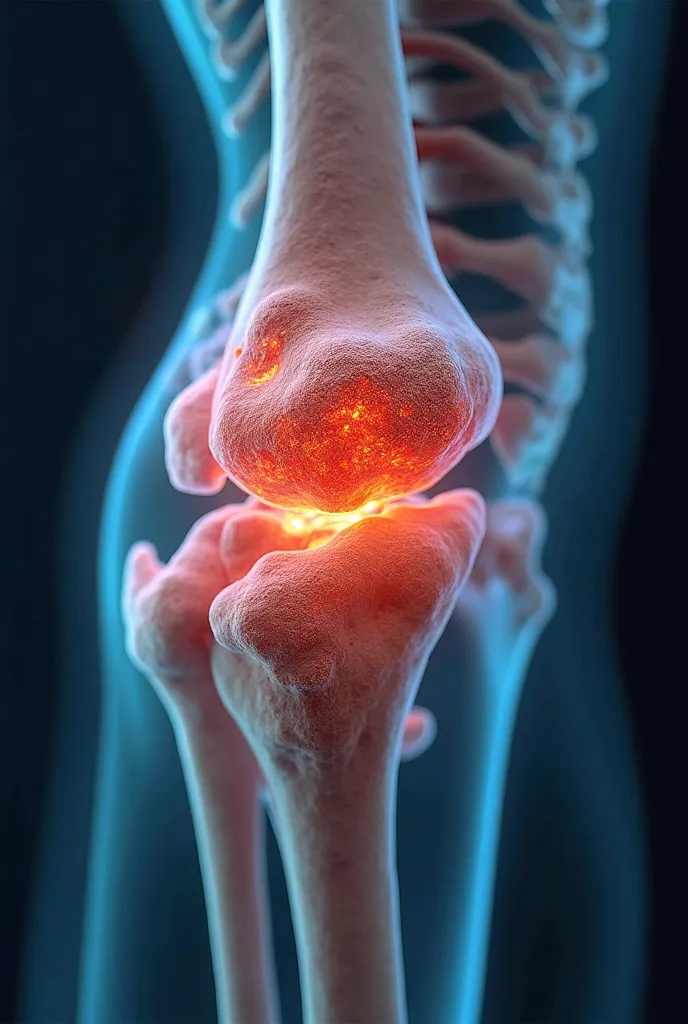

Create a realistic image depicting muscle pain in the leg. Show a person in a na

Create a realistic image depicting muscle pain in the leg. Show a person in a natural posture, with one hand placed on the area where you feel muscle pain. The area of pain should be highlighted with a reddish hue to indicate discomfort.. The person's expression should reflect mild distress or discomfort.. The image must have realistic skin textures and lighting., and the background should be neutral to focus attention on the person and the highlighted area of pain

Create a realistic image depicting muscle pain in the leg

Show a person in a natural posture

with one hand placed on the area where you feel muscle pain

The area of pain should be highlighted with a reddish hue to indicate discomfort

s expression should reflect mild distress or discomfort

The image must have realistic skin textures and lighting

and the background should be neutral to focus attention on the person and the highlighted area of pain